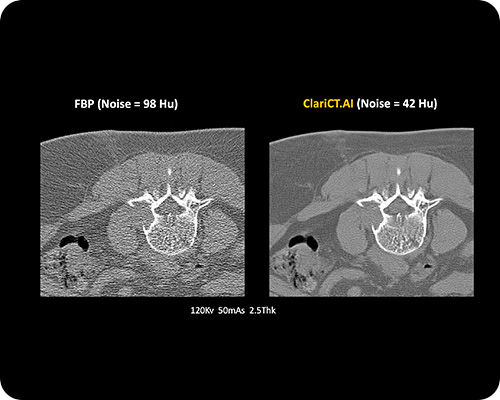

ClariCT.AI

AI-Powered Radiation Reduction

The first AI software that dramatically reduces radiation exposure while delivering the highest quality CT images using advanced AI denoising technology.

Reduces radiation exposure by 70-95% while maintaining superior image quality